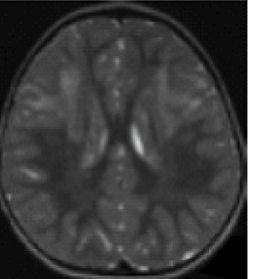

- Periventricular rim abnormalities (eg, high T1-weighted signal and low T2-weighted signal)1

Unlike multiple sclerosis, Alexander disease is not associated with generalized brain atrophy23; it may also be distinguished by the presence of symmetrical lesions on MRI.54 A spectrum of atypical MRI findings, including ventricular garlands, swelling of the medulla, tumor-like presentations, and inflammatory features, have also been documented.55-61

An additional imaging pattern characterized by bilateral symmetric hyperintensity on T2-weighted imaging involving the central inferior olivary nucleus, the pyramids, and the cuneate and gracile fascicles, with sparing of the peripheral inferior olivary nucleus and inferior peduncle (termed the “chipmunk sign”), is a common feature in people with Alexander disease regardless of age of onset.62